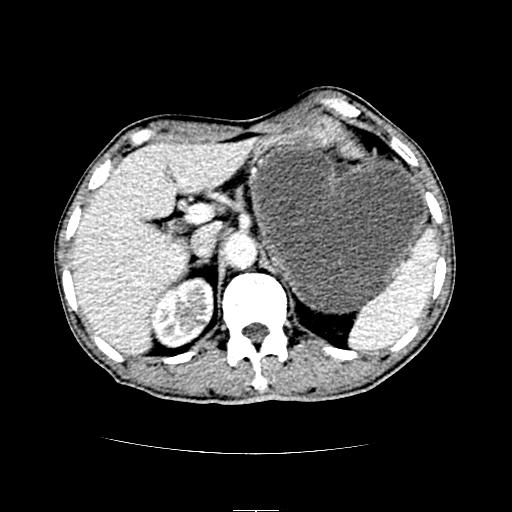

左上腹胃、脾及胰腺间巨大囊性占位性病变,内见多数薄隔,有轻度强化,明显占位效应。左肾见一小囊肿。

考虑:1、左上腹巨大囊肿(可能来源于胰腺)。

2、左肾小囊肿。

左上腹胃、脾及胰腺间巨大囊性占位性病变,内见多数薄隔,有轻度强化,明显占位效应,胰腺及左肾结构清楚,明显向后下方推压 移位。左肾见一小囊肿.多考虑:1 网膜巨大囊肿。2 左肾小囊肿。

1胃脾胰之间一巨大囊性影,胃明显向前推移,胰体尾部似肥大,考虑囊性影来源于胰腺(假性囊肿?)2左肾小囊肿。

左上腹囊性占位,与胰腺分界不清,考虑起源于胰腺可能。

左上腹囊性占位,虽与胰腺分界不清,胰尾似乎受压前移,病灶最大截面并不在胰腺水平,考虑来源于网膜可能性大吧,应再详细追问病史.

左上腹胃、脾及胰腺间巨大囊性占位性病变,其内见多数薄隔,有轻度强化,明显占位效应。左肾见一小囊性变。

左肾囊肿;网膜巨大囊肿。